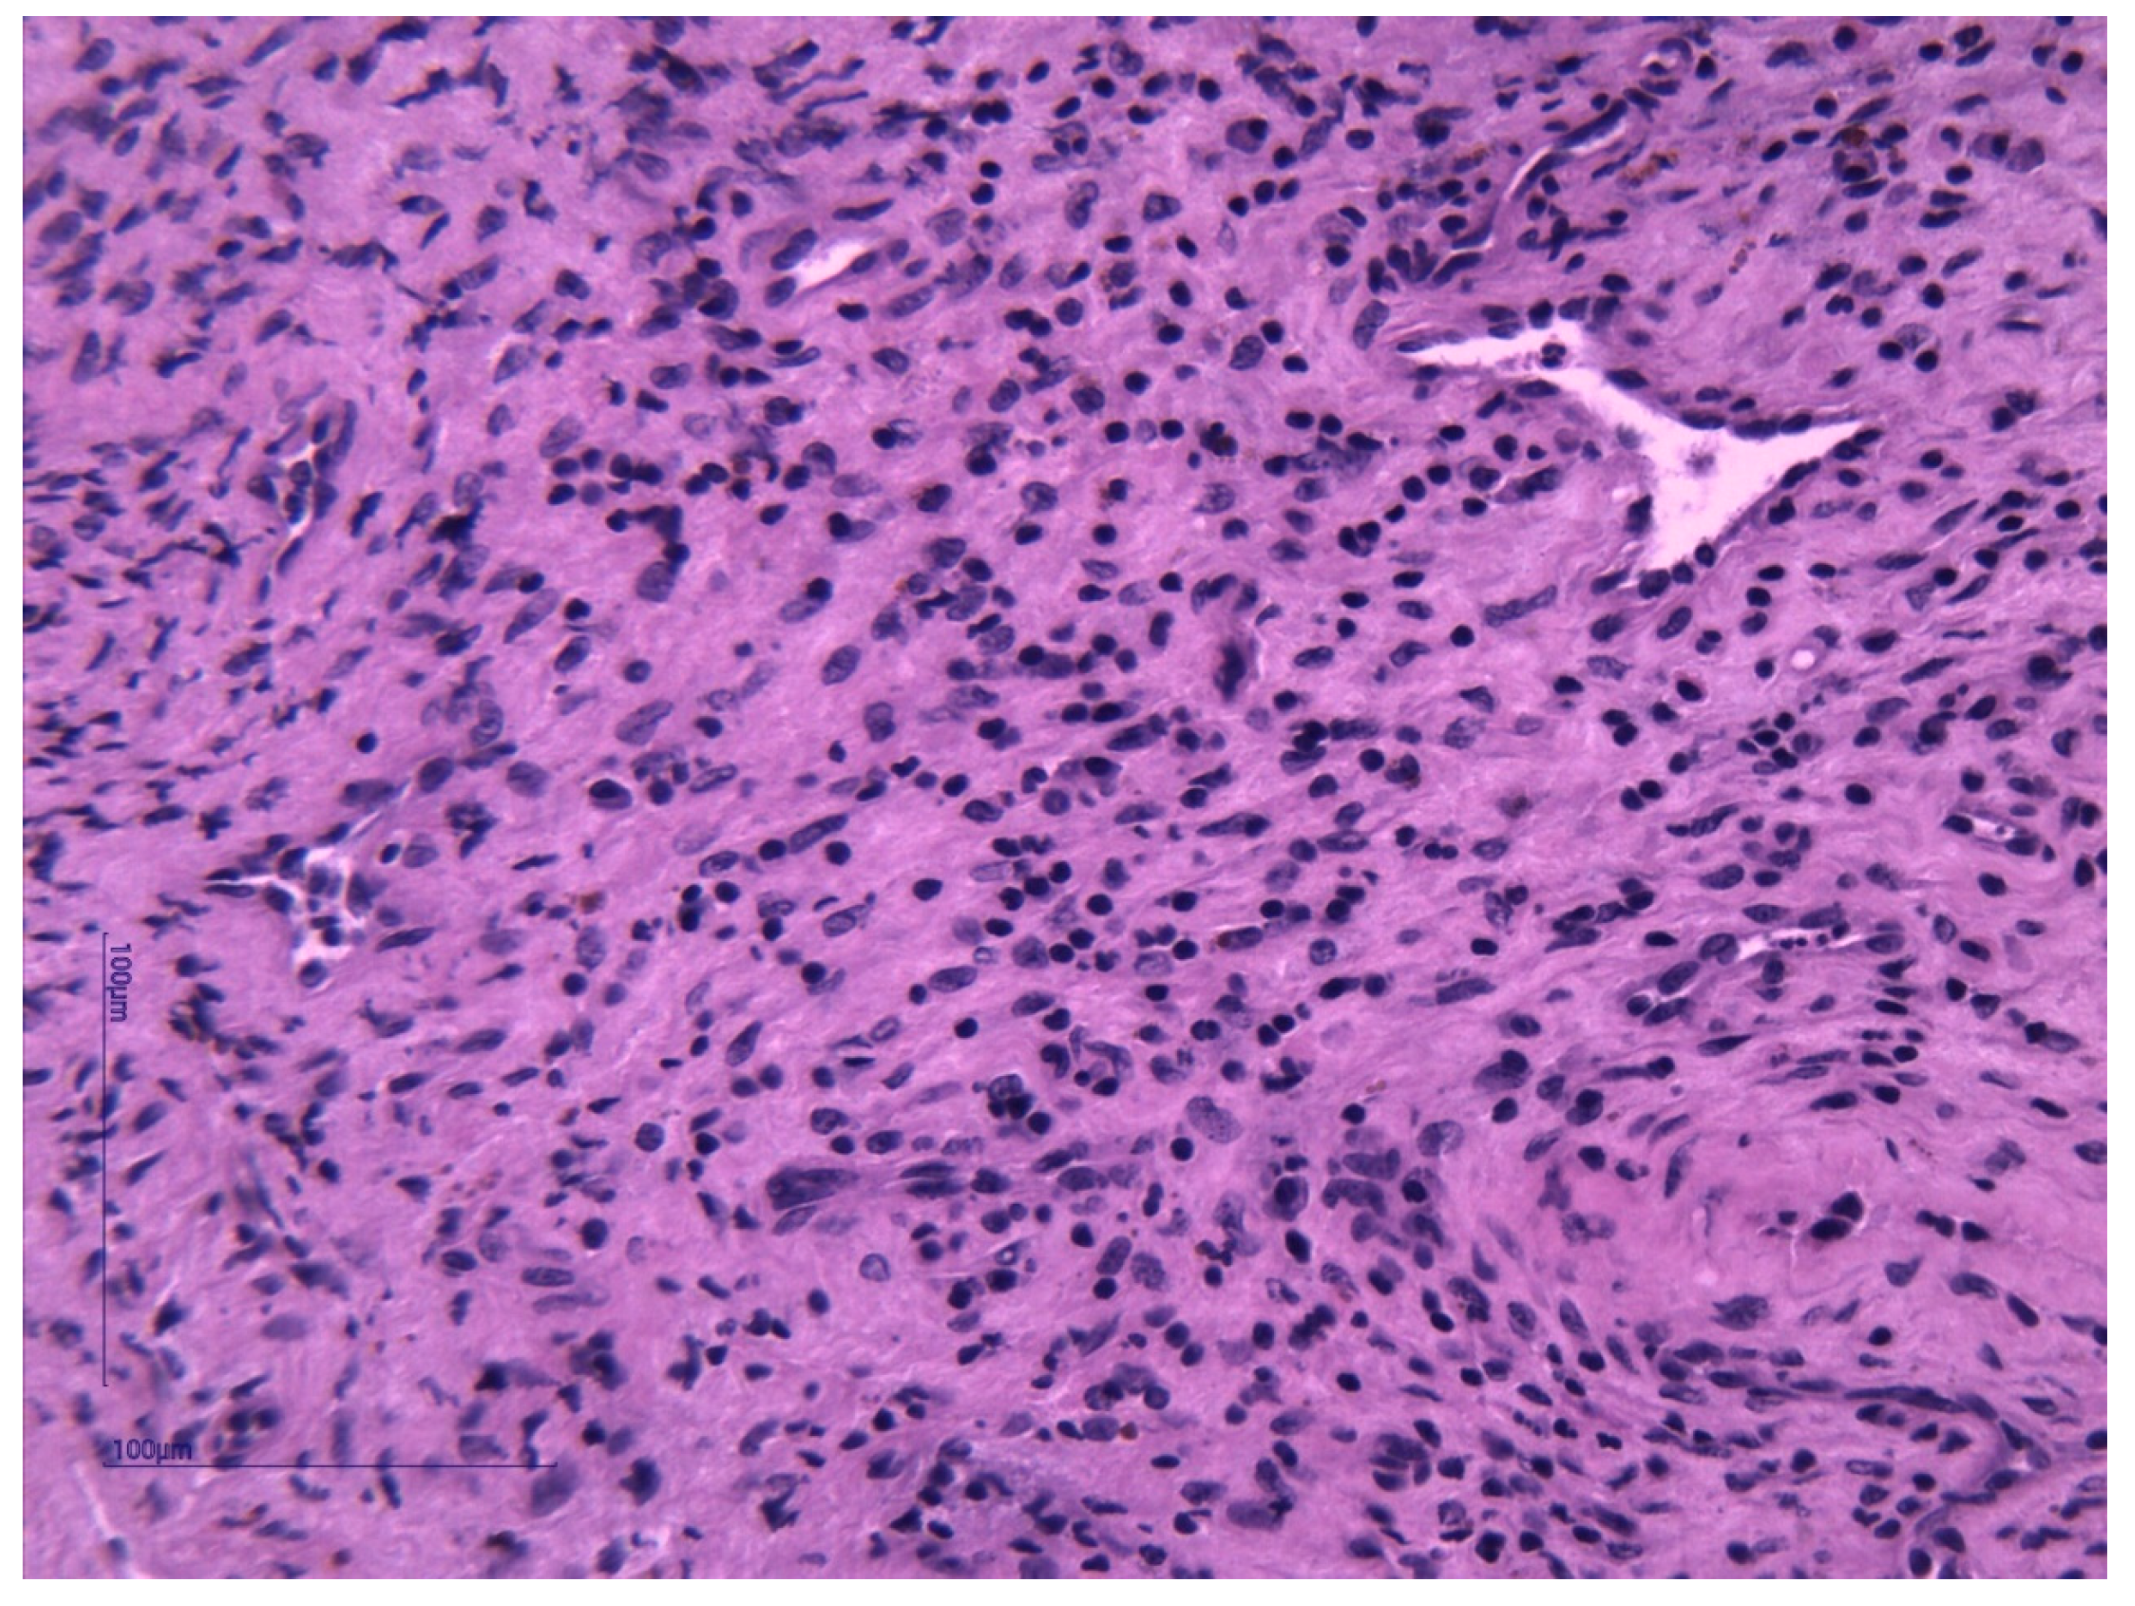

Histopathological examination and immunohistochemistry established the diagnosis of capillary hemangioma with desmoplastic stroma. The pathologist described, on hematoxylin–eosin (HE) staining, tumor proliferation composed of endothelial cells without atypia, forming delicate vascular structures without lumens. The aspect was of a benign vascular proliferation formed by endothelial cells that form fragile submucosal vascular structures; some vessels appeared slightly dilated and with intraluminal red blood cells (Figure 3 and Figure 4). The pathologic assessment did not identify any ulcerations. Immunohistochemical analysis of the tumor showed that it was CD31- and CD34-positive, with Ki67 < 1%. Both immunohistochemical markers CD31 and CD34 are positive in endothelial cells, but CD31 is considered the most dependable endothelial marker [9].

Figure 3. Solid area from a capillary hemangioma represented by a tumor proliferation composed of endothelial cells without atypia forming vascular structures without lumens. HE stain, ×400.